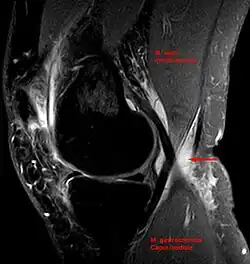

Baker's cyst on MRI, sagittal image -